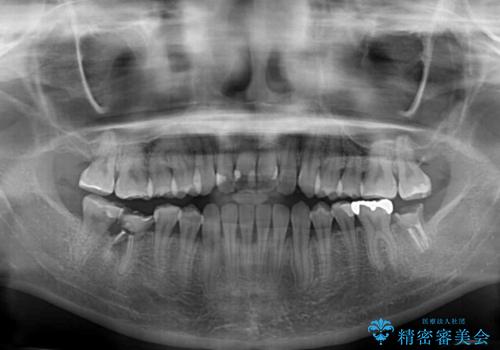

- 上下前歯の開咬とデコボコを気にして来院された患者様です。

開咬(オープンバイト)はインビザラインによる矯正治療がワイヤー装置と比べて圧倒的に有利であるため、インビザラインによる矯正治療を行うこととしました。

通院されなかった時期があって治療期間が長くなったり、奥歯に抜歯が必要な歯があったりと、治療は一筋縄にはいきませんでしたが、何とか治療を終えることができました。

今後はインプラント治療やむし歯治療を進めて行く予定です。